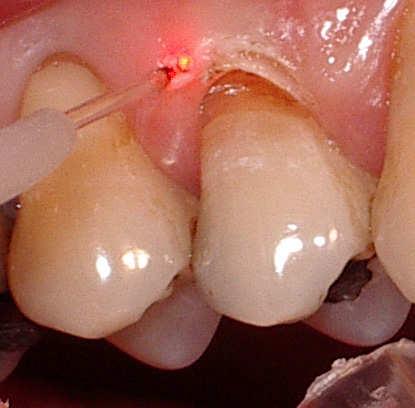

A palatal view of a maxillary premolar during a

crown lengthening procedure.

Crown lengthening is a surgical procedure performed by a dentist to expose a greater amount of tooth structure for the purpose of subsequently restoring the tooth prosthetically. This is done by incising the gingival tissue around a tooth and, after temporarily displacing the soft tissue, predictably removing a given height of alveolar bone from the circumference of the tooth or teeth being operated on. While many general dentists perform this procedure, they frequently refer such cases to periodontists.